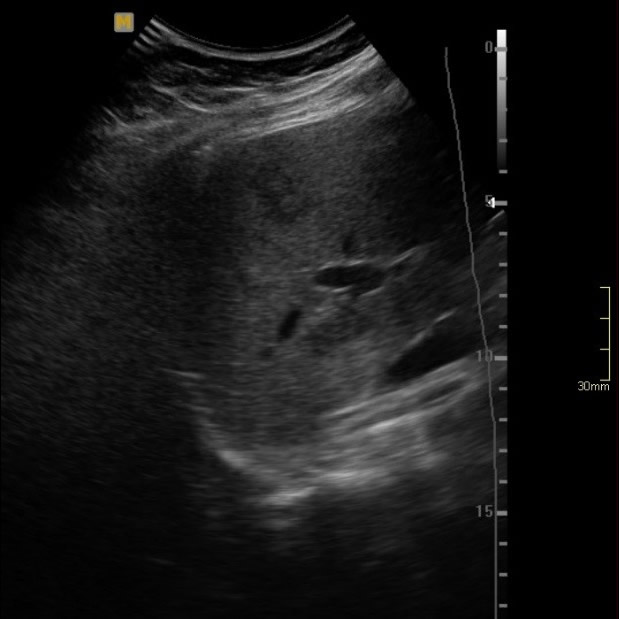

Abril 2019. Hospital Privado Paciente femenina de 41 años con dolor abdominal y deposiciones blandas. APP: sana previa